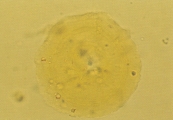

Кальция карбонат может кристаллизоваться в моче лошадей, кроликов, коз, образуя большие желто-коричневые или бесцветные сфероиды с радиальной исчерченностью, или маленькие кристаллы круглой, овальной или гантелеобразной формы (рис. 2 и 3). У собак и кошек эти кристаллы обычно не обнаруживаются. Если в моче обнаруживается гантелеобразный кристалл, то это скорее кальция оксалат моногидрат.

Рис. 2. Микрофотография кристаллов кальция карбоната в мочевом осадке 7-летней кобылы (не окрашено, увеличение Х160